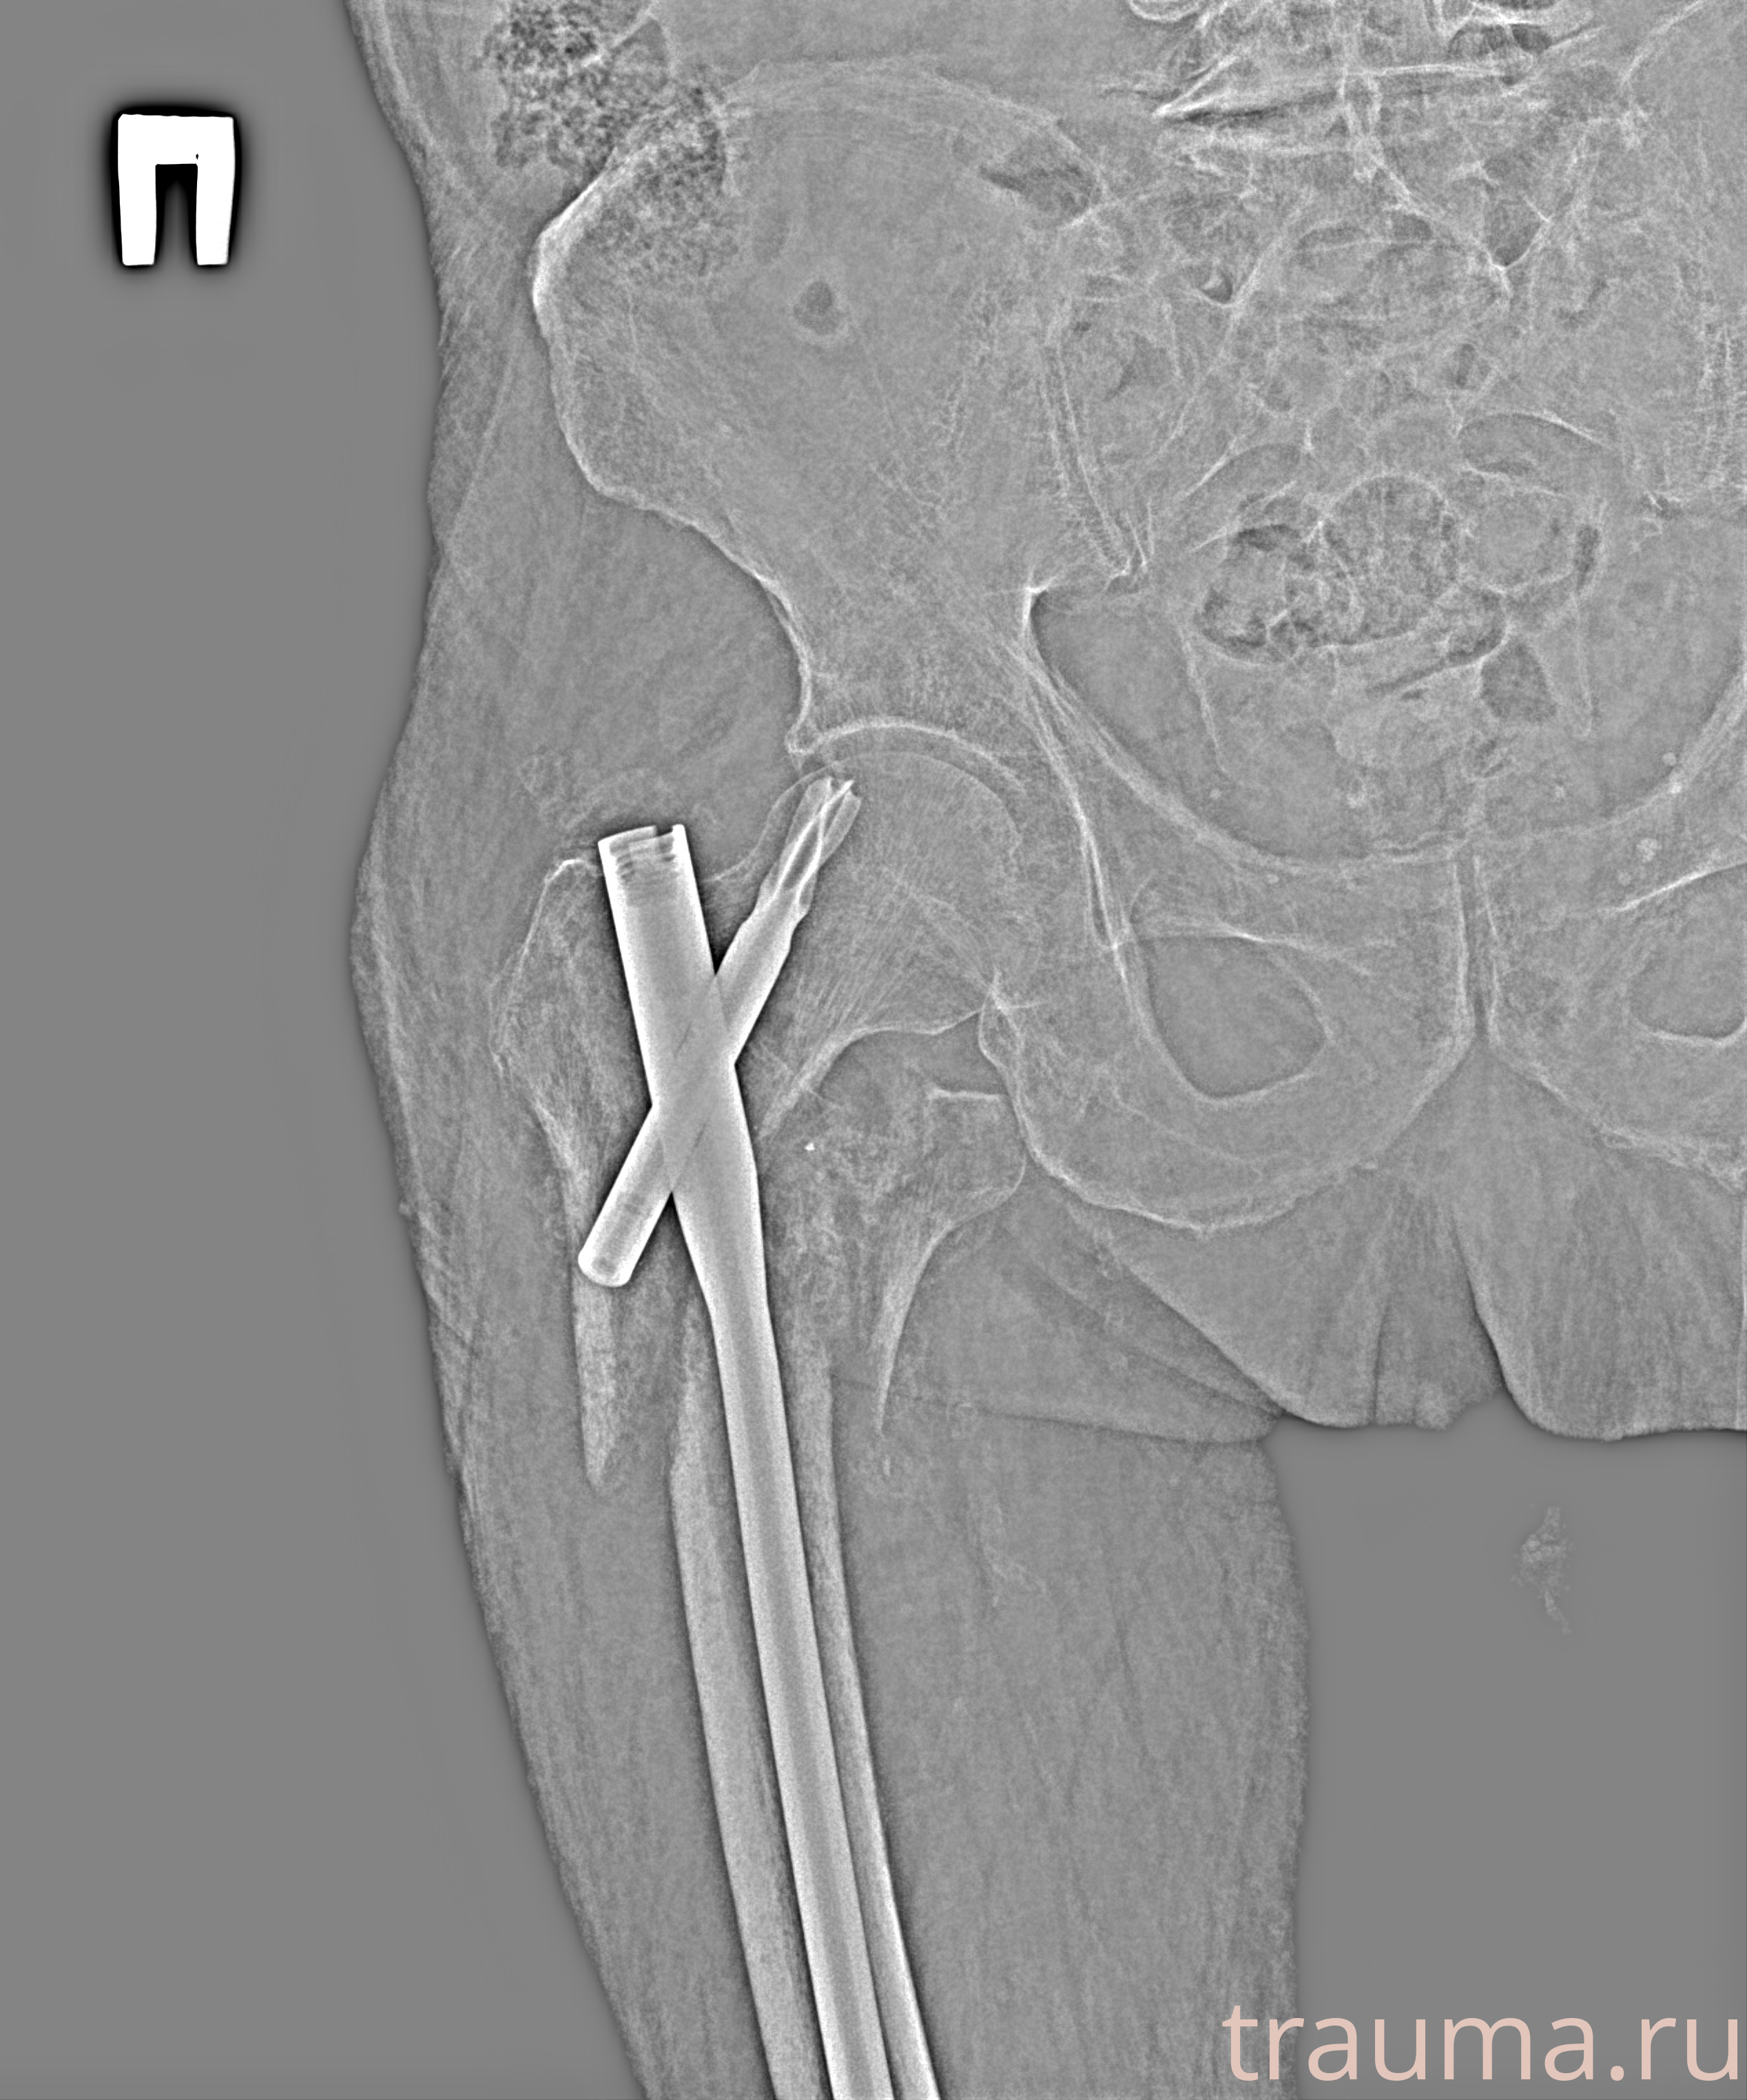

Первая помощь при переломе шейки бедра

Рентген на дому: по вашему адресу приезжает врач-рентгенолог, травматолог-ортопед с мобильным рентгеновским аппаратом, проводит диагностику травмы или заболевания, делает необходимые рентгенограммы, дает рекомендации по дальнейшему лечению. Получить качественные снимки в домашних условиях возможно благодаря уникальной методике, разработанной МосРентген Центром для института  Склифосовского